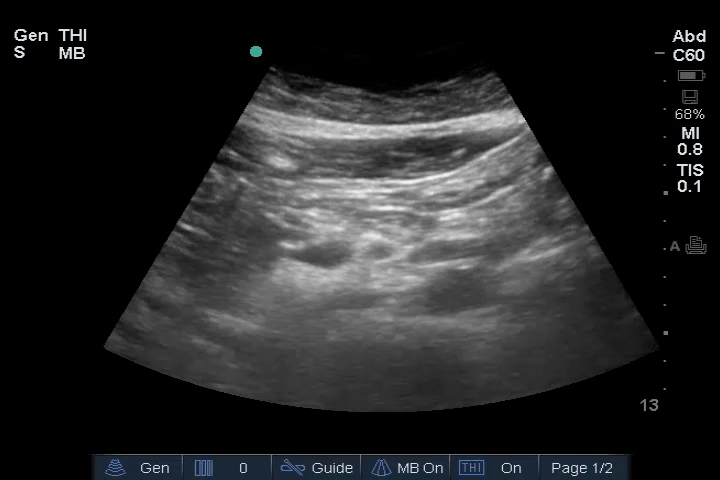

20_Abdomen_RUQ_Perihepatic (normal)